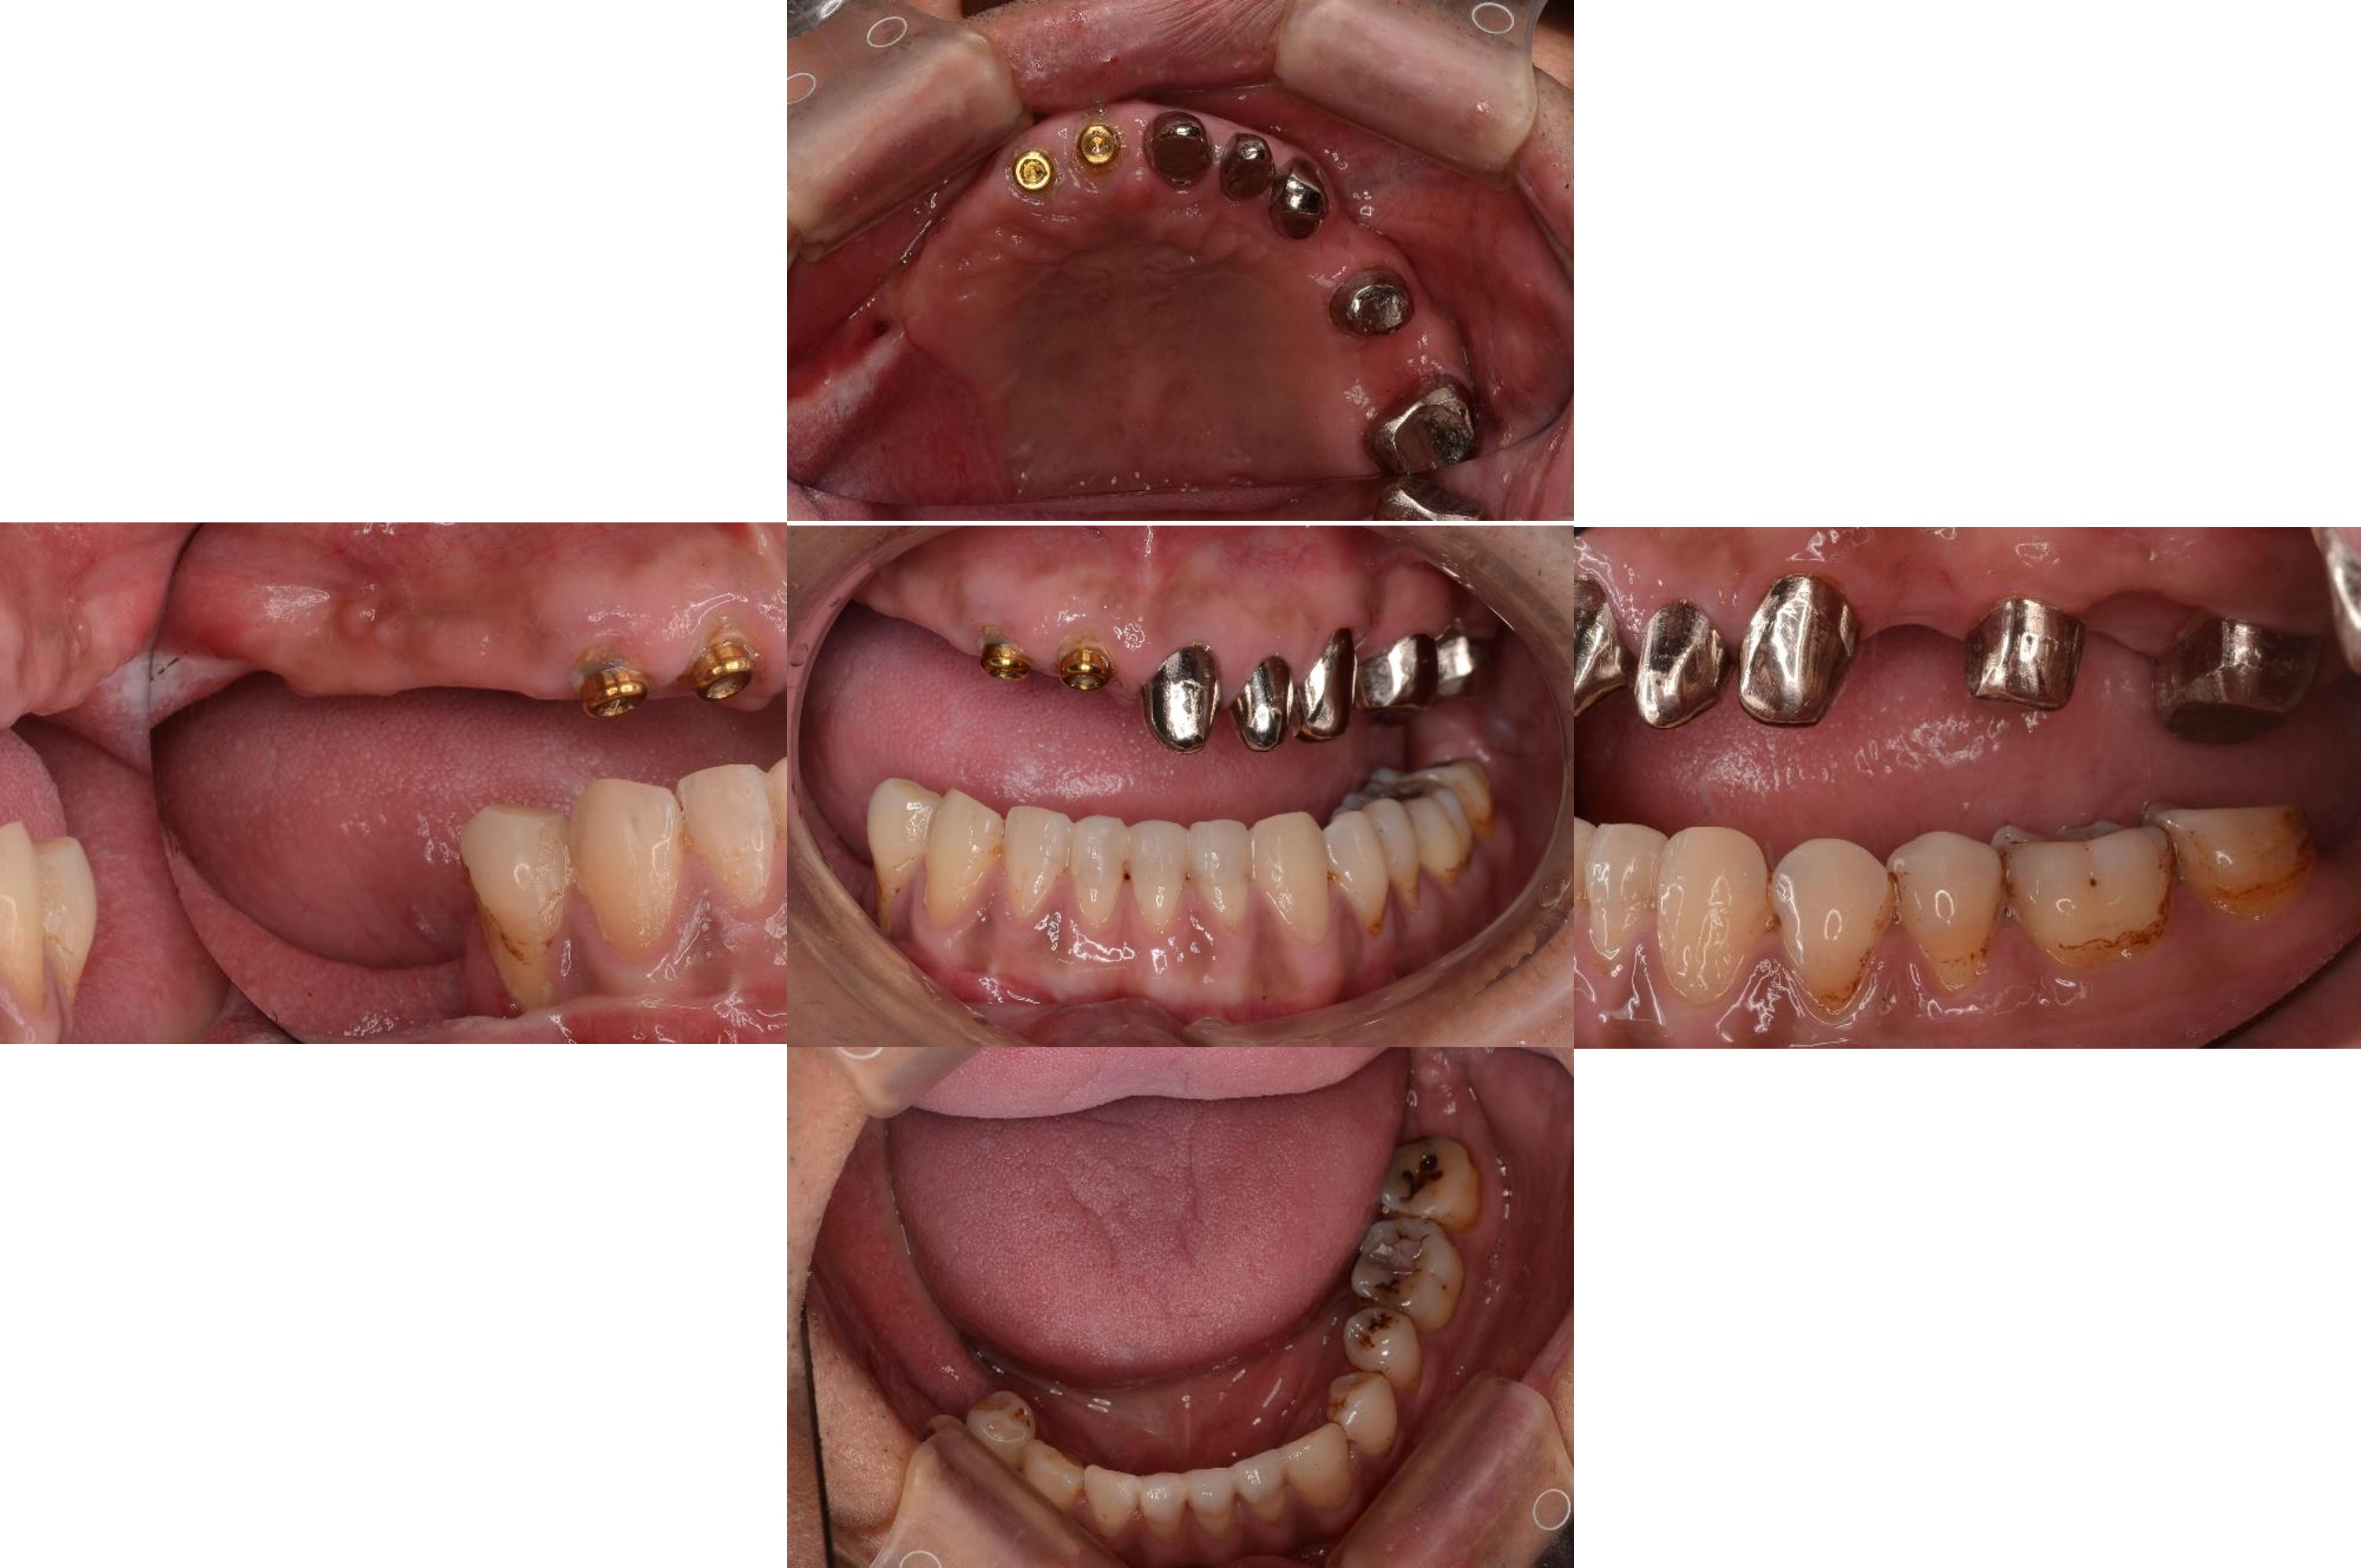

治療前上下顎因口外手術,造成咬合喪失

治療前,咬合喪失,磨耗

治療前,殘根與牙周支撐不良